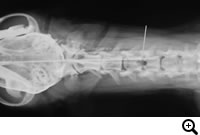

馬尾症候群

症状:背部痛、慢性的な後肢跛行、後肢の爪先をひきずる、段差の上り下りを嫌うなど

馬尾症候群とは

腰仙椎領域で肥厚した椎間板の線維輪などによって、神経根が圧迫されている状態です。痛みや神経症状をともないます。

診断

レントゲン検査、脊髄造影検査、CT検査、MRI検査

治療

Dorsalnectomyという腰仙椎に窓をつくり、神経根の圧迫を取り除く手術などをおこないます。